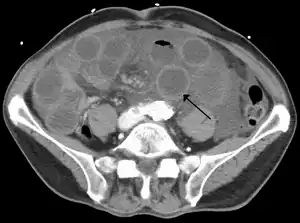

| Método de diagnóstico | Angiografia, tomografia computadorizada[1] |

Fatores de risco incluem fibrilação auricular, insuficiência cardíaca, insuficiência renal crônica, sendo propenso à formação de coágulos de sangue, e infarto do miocárdio anteriores.[2] Existem quatro mecanismos pelos quais a má circulação sanguínea ocorre: um coágulo de sangue a partir de outro local ficando alojado em uma artéria, uma nova formação de coágulo de sangue em uma artéria, um coágulo de sangue se formando na veia mesentérica superior, e o fluxo insuficiente de sangue devido a pressão arterial baixa ou espasmos das artérias.[3][4] A doença crônica é um fator de risco para doença aguda.[5] O melhor método diagnóstico é a angiografia, com a tomografia computadorizada a ser utilizada quando esta não está disponível.[1]